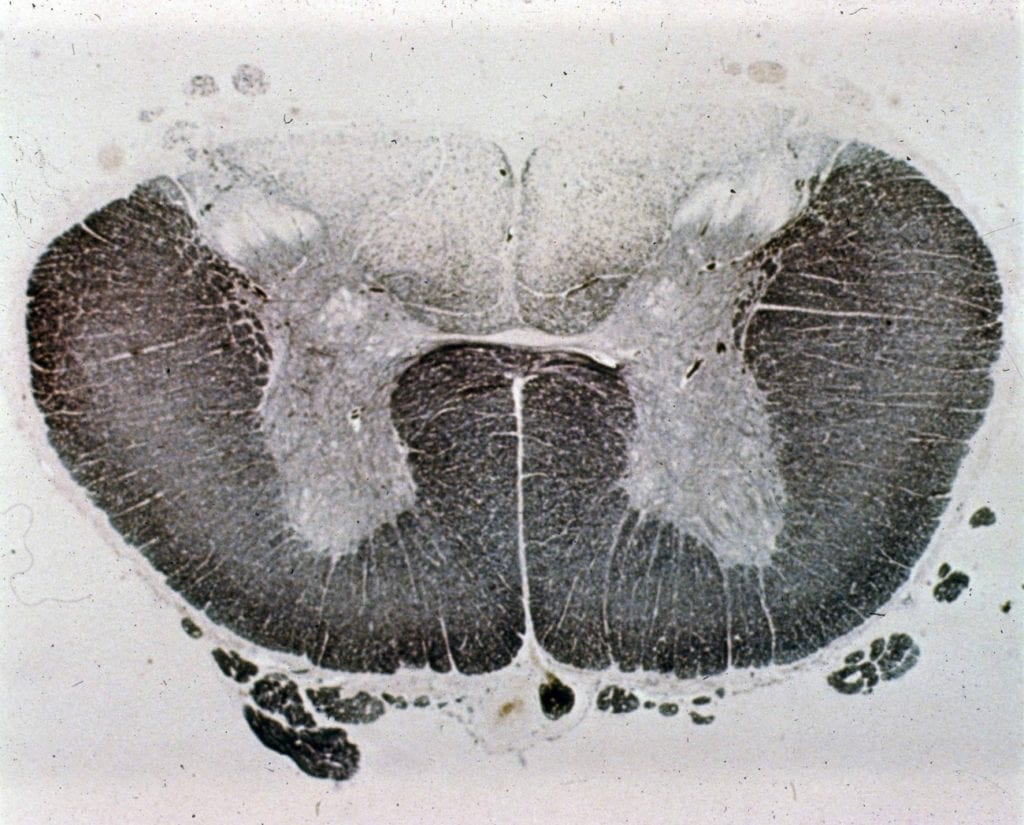

Tabes dorsalis (preparát) WikiSkripta

Tabes dorsalis (preparát) WikiSkripta Tabes Dorsalis Pathology Tabes dorsalis, also known as locomotor ataxia, is a slowly progressive and rare degenerative parenchymatous disease of the. Tabes dorsalis is the result of an untreated syphilis infection. Tabes dorsalis is a slowly progressive parenchymatous degenerative disease involving the posterior columns (ie,. Tabes dorsalis (locomotor ataxia) is characterized by atrophy of lumbar posterior nerve roots and sometimes the optic nerves,. Tabes Dorsalis Pathology.